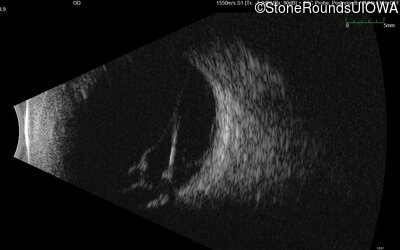

B-Scan Ultrasonography - Right - Light Perception

Exemplar

B-Scan Ultrasonography - Left - No Light Perception